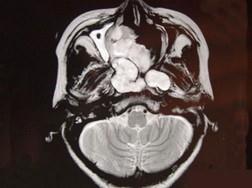

问题 女性,41岁,鼻腔流脓涕3年,鼻部面部肿胀1年,近来加重,MRI检查如图,请选择最可能诊断 ( )

选项 A、鼻咽癌 B、鼻腔血管瘤 C、鼻腔内出血 D、鼻腔软骨瘤 E、鼻腔内囊肿

答案 D